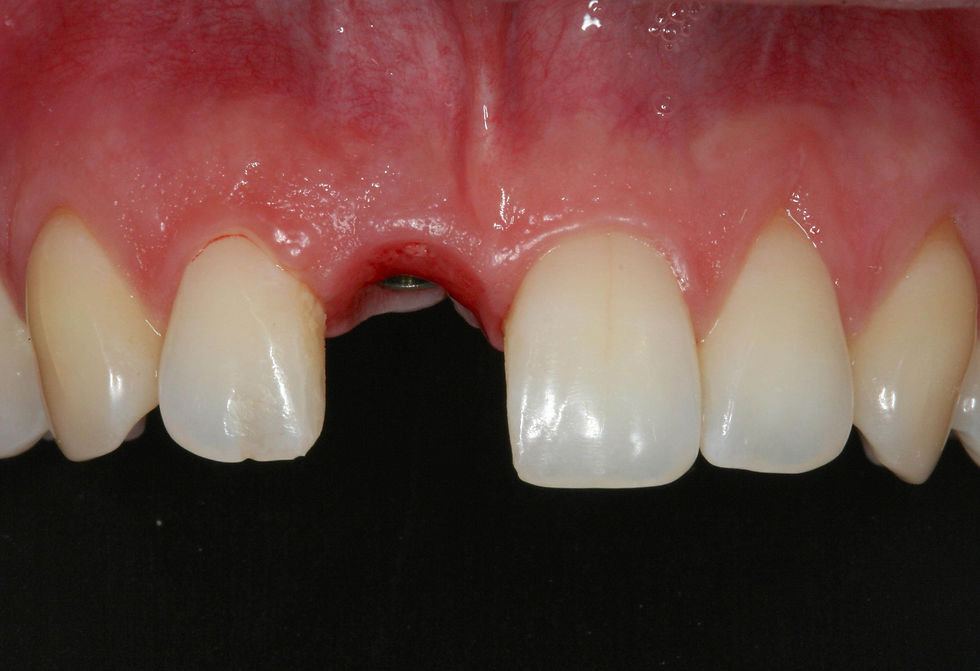

After 5 months from the extraction, the guided surgery implant positioning is planned. Frontal clinical image shows that the distal papilla of the site 1.1 is more apical than the mesial and the contralateral papillae.